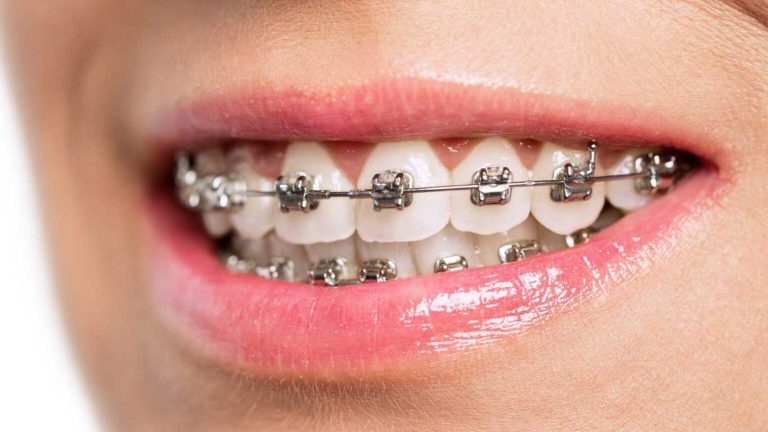

درمان ارتودنسی نقش کلیدی در اصلاح اپن بایت دارد. بسته به شرایط بیمار و شدت ناهنجاری، از روش های مختلفی برای اصلاح اپن بایت استفاده می شود:

- ارتودنسی فک بالا و یا ارتودنسی فک پایین: در بسیاری از موارد، تنها اصلاح وضعیت فک بالا یا پایین می تواند به طور مؤثری مشکل بایت باز را رفع کند. این درمان ها به طور خاص برای افرادی که تنها یک فک آنها نیاز به اصلاح دارد، مناسب است.

- استفاده از براکت ارتودنسی همراه با کش ارتودنسی: در این روش، از براکت های فلزی یا سرامیکی به همراه کش های مخصوص برای اصلاح موقعیت دندان ها و فک ها استفاده می شود. کش های ارتودنسی به فک ها فشار می آورند تا به تدریج در موقعیت درست قرار گیرند.

- بهره گیری از ارتودنسی سرامیکی برای حفظ زیبایی: در این روش، از براکت های سرامیکی به جای براکت های فلزی استفاده می شود که با رنگ دندان هم خوانی دارد و برای کسانی که نگران ظاهر خود هستند، گزینه بهتری است.

- بهره گیری از انواع ارتودنسی دندان شامل ارتودنسی متحرک و ارتودنسی ثابت: برای درمان بایت باز می توان از ارتودنسی متحرک (که بیمار خود می تواند آن را خارج کند) یا ارتودنسی ثابت (که به طور دائم به دندان ها متصل است) استفاده کرد. انتخاب روش به سن بیمار و شدت ناهنجاری بستگی دارد.